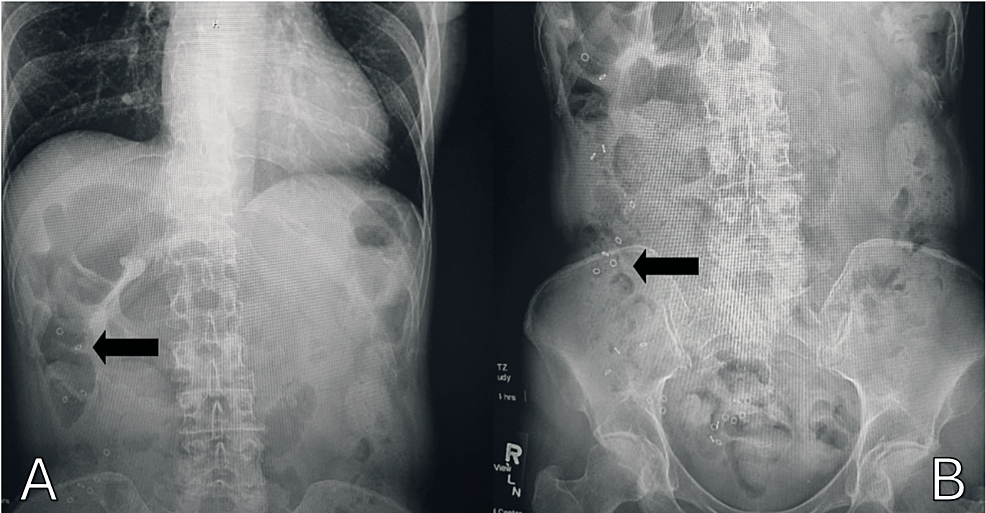

Sitz Markers Xray . By counting the markers and. Sitz mark study in a child with chronic constipation. This can be useful if she or he. The sitz marker study allows the gastroenterologist to grossly quantify the speed of colonic transit. The sitz or plastic marker study for colonic transit has been around for many years. Our team of specialized doctors, nurses and technologists perform sitz marker studies to see how fast food is moving through the intestines. It is most often used for patients. To evaluate motility through the gi tract, two techniques are used:

Sitz Markers Xray The sitz marker study allows the gastroenterologist to grossly quantify the speed of colonic transit. The sitz or plastic marker study for colonic transit has been around for many years. It is most often used for patients. This can be useful if she or he. Sitz mark study in a child with chronic constipation. To evaluate motility through the gi tract, two techniques are used: The sitz marker study allows the gastroenterologist to grossly quantify the speed of colonic transit. Our team of specialized doctors, nurses and technologists perform sitz marker studies to see how fast food is moving through the intestines. By counting the markers and.

How to use a plain abdominal radiograph in children with functional Sitz Markers Xray By counting the markers and. Sitz mark study in a child with chronic constipation. To evaluate motility through the gi tract, two techniques are used: Our team of specialized doctors, nurses and technologists perform sitz marker studies to see how fast food is moving through the intestines. It is most often used for patients. The sitz marker study allows the. Sitz Markers Xray.

How to use a plain abdominal radiograph in children with functional Sitz Markers Xray The sitz marker study allows the gastroenterologist to grossly quantify the speed of colonic transit. By counting the markers and. To evaluate motility through the gi tract, two techniques are used: It is most often used for patients. Sitz mark study in a child with chronic constipation. Our team of specialized doctors, nurses and technologists perform sitz marker studies to. Sitz Markers Xray.